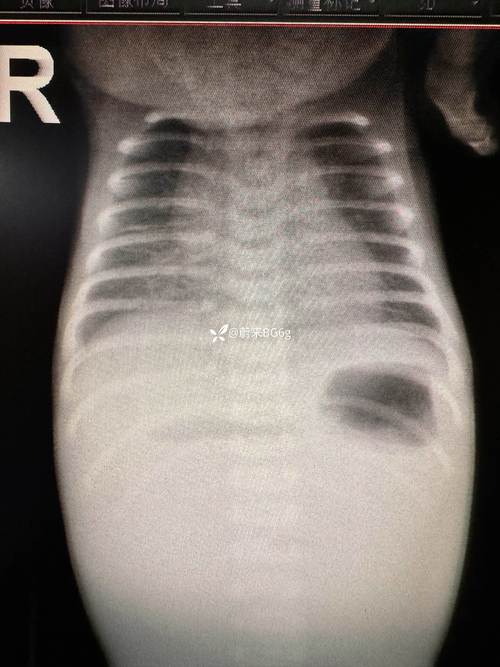

- 诊断肺部疾病: 这是新生儿X光最常用的用途,新生儿肺炎、肺透明膜病、湿肺、气胸等,通过X光可以快速、准确地诊断,这对于指导治疗(如是否需要使用呼吸机、抗生素)至关重要。

- 诊断消化道问题: 新生儿呕吐、腹胀,可能是由先天性消化道畸形(如先天性巨结肠、肠旋转不良)或胎粪性肠梗阻引起的,X光(尤其是腹部立位片)是诊断这些急症的首选方法。